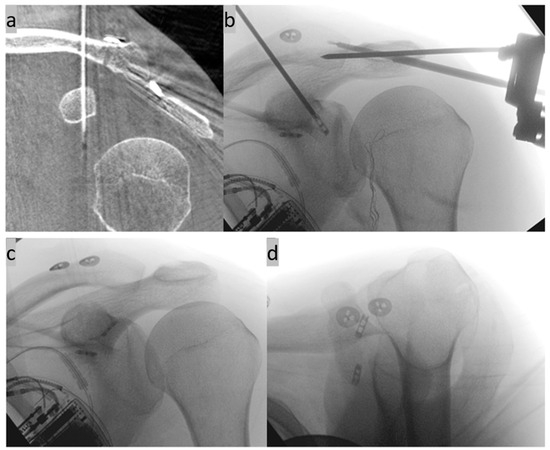

2. Surgical Technique

3. Possible Applications and Extensions of the New Method

- Böhringer, A.; Gebhard, F.; Dehner, C.; Eickhoff, A.; Cintean, R.; Pankratz, C.; Schütze, K. 3D C-arm navigated acromioclavicular joint stabilization. Arch. Orthop. Trauma. Surg. 2023, 144, 601–610. [Google Scholar] [CrossRef]